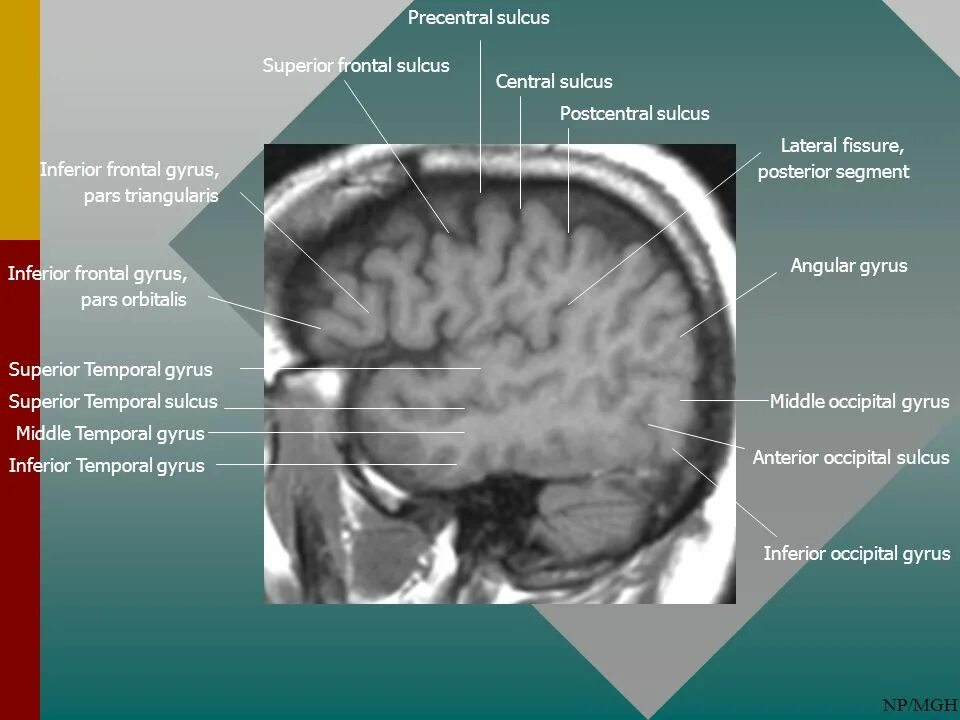

Pars orbitalis